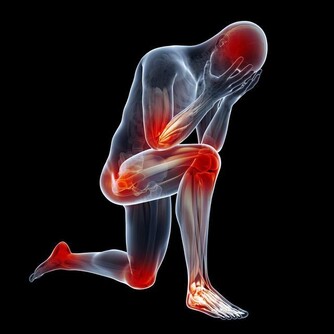

在中醫理論中,造成水腫的原因很多,除了器質性病變(例如腎臟病、心臟病等)之外,肺、脾、腎等3個臟腑功能失調,都容易引發水腫,治療上需辯證論治,視個人體質和症狀表現再對症下藥,量身處方才能有效消除水腫,擺脫虛胖,變得健康又美麗。